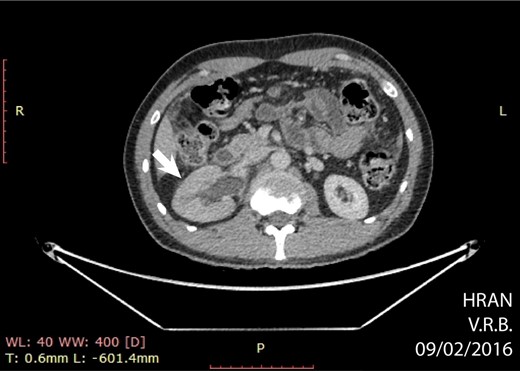

The surgery was indicated at the moment of clinical diagnosis, dismissing any imaging techniques. Even though CT-scanning is not mandatory, it grants over 90% sensitivity and specificity for acute appendicitis and helps with other differential diagnoses [6]. In this case, the CT-scan was only solicited after the lymphoma diagnosis, revealing a bulky and extensive mass in the right iliac fossa, poorly delimited, along with right pyeloureteral dilation. A probable diagnosis of appendiceal neoplasms can be made based on the increased diameter of the appendix shown on CT-scans (>3 cm), which is out of proportion for a non-tumoral appendicitis [5]. The specificity for lymphoma increases when abdominal lymphadenopathy or aneurysmal dilation of the appendiceal lumen are present [7]. These findings corroborate with a pre-operative suspicion of a primary appendiceal neoplasm.

Axial CT showing hydronephrosis by compression of the tumor (arrow) (02/09/16).